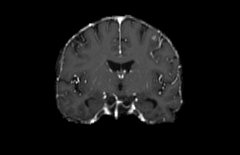

Objectives: This work aims to explore the impact of multicenter data heterogeneity on deep learning brain metastases (BM) autosegmentation performance, and assess the efficacy of an incremental transfer learning technique, namely learning without forgetting (LWF), to improve model generalizability without sharing raw data. Materials and methods: A total of six BM datasets from University Hospital Erlangen (UKER), University Hospital Zurich (USZ), Stanford, UCSF, NYU and BraTS Challenge 2023 on BM segmentation were used for this evaluation. First, the multicenter performance of a convolutional neural network (DeepMedic) for BM autosegmentation was established for exclusive single-center training and for training on pooled data, respectively. Subsequently bilateral collaboration was evaluated, where a UKER pretrained model is shared to another center for further training using transfer learning (TL) either with or without LWF. Results: For single-center training, average F1 scores of BM detection range from 0.625 (NYU) to 0.876 (UKER) on respective single-center test data. Mixed multicenter training notably improves F1 scores at Stanford and NYU, with negligible improvement at other centers. When the UKER pretrained model is applied to USZ, LWF achieves a higher average F1 score (0.839) than naive TL (0.570) and single-center training (0.688) on combined UKER and USZ test data. Naive TL improves sensitivity and contouring accuracy, but compromises precision. Conversely, LWF demonstrates commendable sensitivity, precision and contouring accuracy. When applied to Stanford, similar performance was observed. Conclusion: Data heterogeneity results in varying performance in BM autosegmentation, posing challenges to model generalizability. LWF is a promising approach to peer-to-peer privacy-preserving model training.